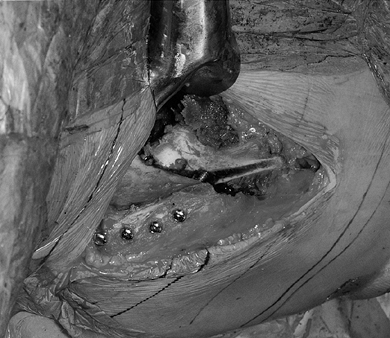

superior pubic ramus with a Gigli saw (Fig. 104.10).

Figure 104.10. Perform an osteotomy of the superior pubic ramus by exposing it through the incision (Fig. 104.8, Fig. 104.9)

and placing dual retractors around the pubic bone. A Gigli saw has been

posterior to anterior. -

Next, address the ischium near its

attachment to the body of the ilium 1 cm below the joint. Approach the

ischium underneath the iliopsoas tendon and place the cutting edge of a

specially designed 40° angled osteotome (Synthes, Paoli, PA) in the

proper position under fluoroscopic control using the previously

described double oblique view to ensure that the ischial cut does not

violate the joint space and is oriented in the correct trajectory. This

trajectory is from inferolateral to superomedial. The ischium is not

transected.

Figure 104.11.

For the osteotomy of the ischium, an angled AO (Synthes) osteotome is

positioned under fluoroscopic control to cut it partially through from

inferolateral to superomedial. -

Cut the ilium using an oscillating saw

from the ASIS toward the sciatic notch, stopping 10–15 mm short of the

pelvic brim (iliopectinate line) (Fig. 104.12). Then use a curved standard ½-inch osteotome to cut across the pelvic brim as originally described by Ganz et al. (51).

Next, use the angled Synthes osteotome to cut parallel to the posterior

column intersecting with the previous cut made in the ischium.

Figure 104.12.

Cut the ilium with a power saw from just inferior to the ASIS toward

the sciatic notch, stopping approximately 15 mm above the pelvic brim,

which is marked by the iliopectinate line (refer to Fig. 104.17). -

The final cut frees the acetabulum from

its continuity with the ilium. Insert the angled osteotome into the

medial osteotomy of the quadrilateral surface and transect the ilium

from medial to lateral, carefully avoiding the hip joint. -

Mobilize the free acetabular segment with

an osteotome inserted as a lever into the osteotomy and/or with the aid

of a Schanz screw inserted into the fragment (Fig. 104.13, Fig. 104.14). Ensure that the fragment is completely mobile and then reduce it back to its original position.

Figure 104.13.

After cutting the lamina quadrilatera with an angled Synthes osteotome

(not shown), mobilize the acetabular fragment with the same osteotome.

The osteotome is shown in the iliac osteotomy with the ASIS just above

the osteotome.

Figure 104.14. More extensive anterior mobilization is shown here. -

Arthrotomy of the hip joint may now be

performed with optimum timing since recovery of clear fluid suggests

that the hip joint has not been penetrated. Inspect the labrum of the

hip and resect any tears or detachments (Fig. 104.15).

The capsule may be left open to allow assessment of possible

impingement of the femoral neck caused by anterior reorientation of the

acetabulum.

Figure 104.15. Now re-reduce the acetabulum and perform an anterior arthrotomy to inspect the labrum, which was normal in this hip. -